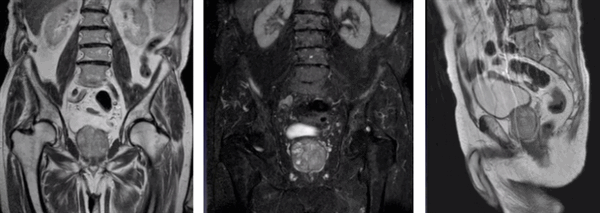

Магнитно-резонансная томограмма: распространение аденокарциномы на семенные пузырьки (стрелка)